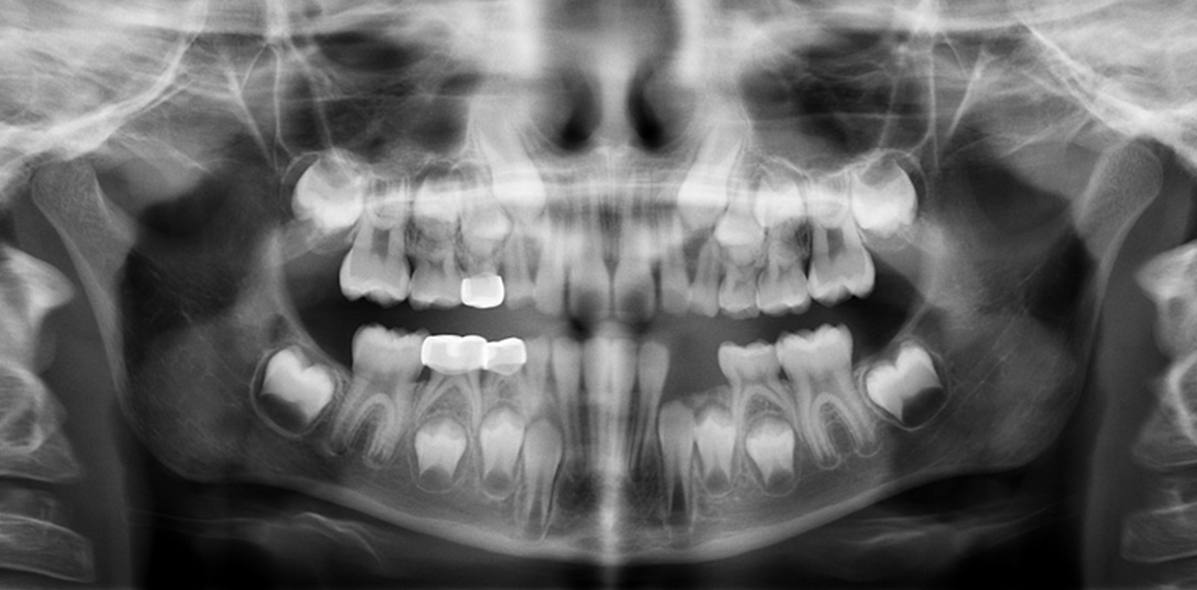

4. How old is the patient with the following X ray?